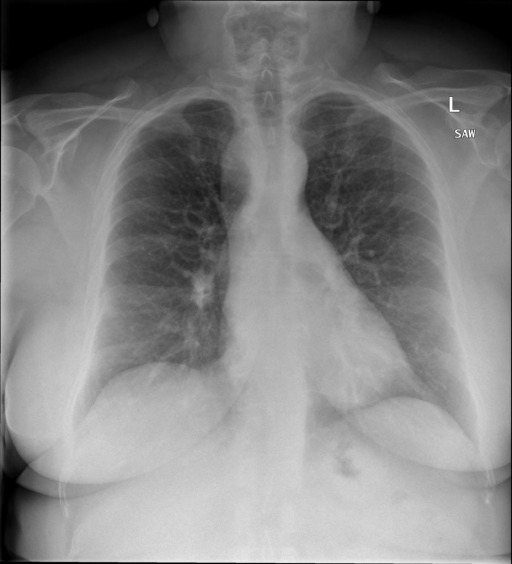

|X光影像|诊疗报告(医生)|XrayGLM|

|:-|:-|:-|

||X光图片显示没有扭曲的区域、可疑的骨质不透明度或胸腺积液。心脏大小轻微增大,但非常稳定。此外,没有气胸的证据,肺野也正常。总体来说,X光片显示没有急性心脏异常,但要注意轻微的心脏扩大。|X光片显示,心脏大小正常。肺部和纵隔轮廓清晰,没有气胸或胸腔积液的证据。骨骼结构完整,没有任何急性异常。|